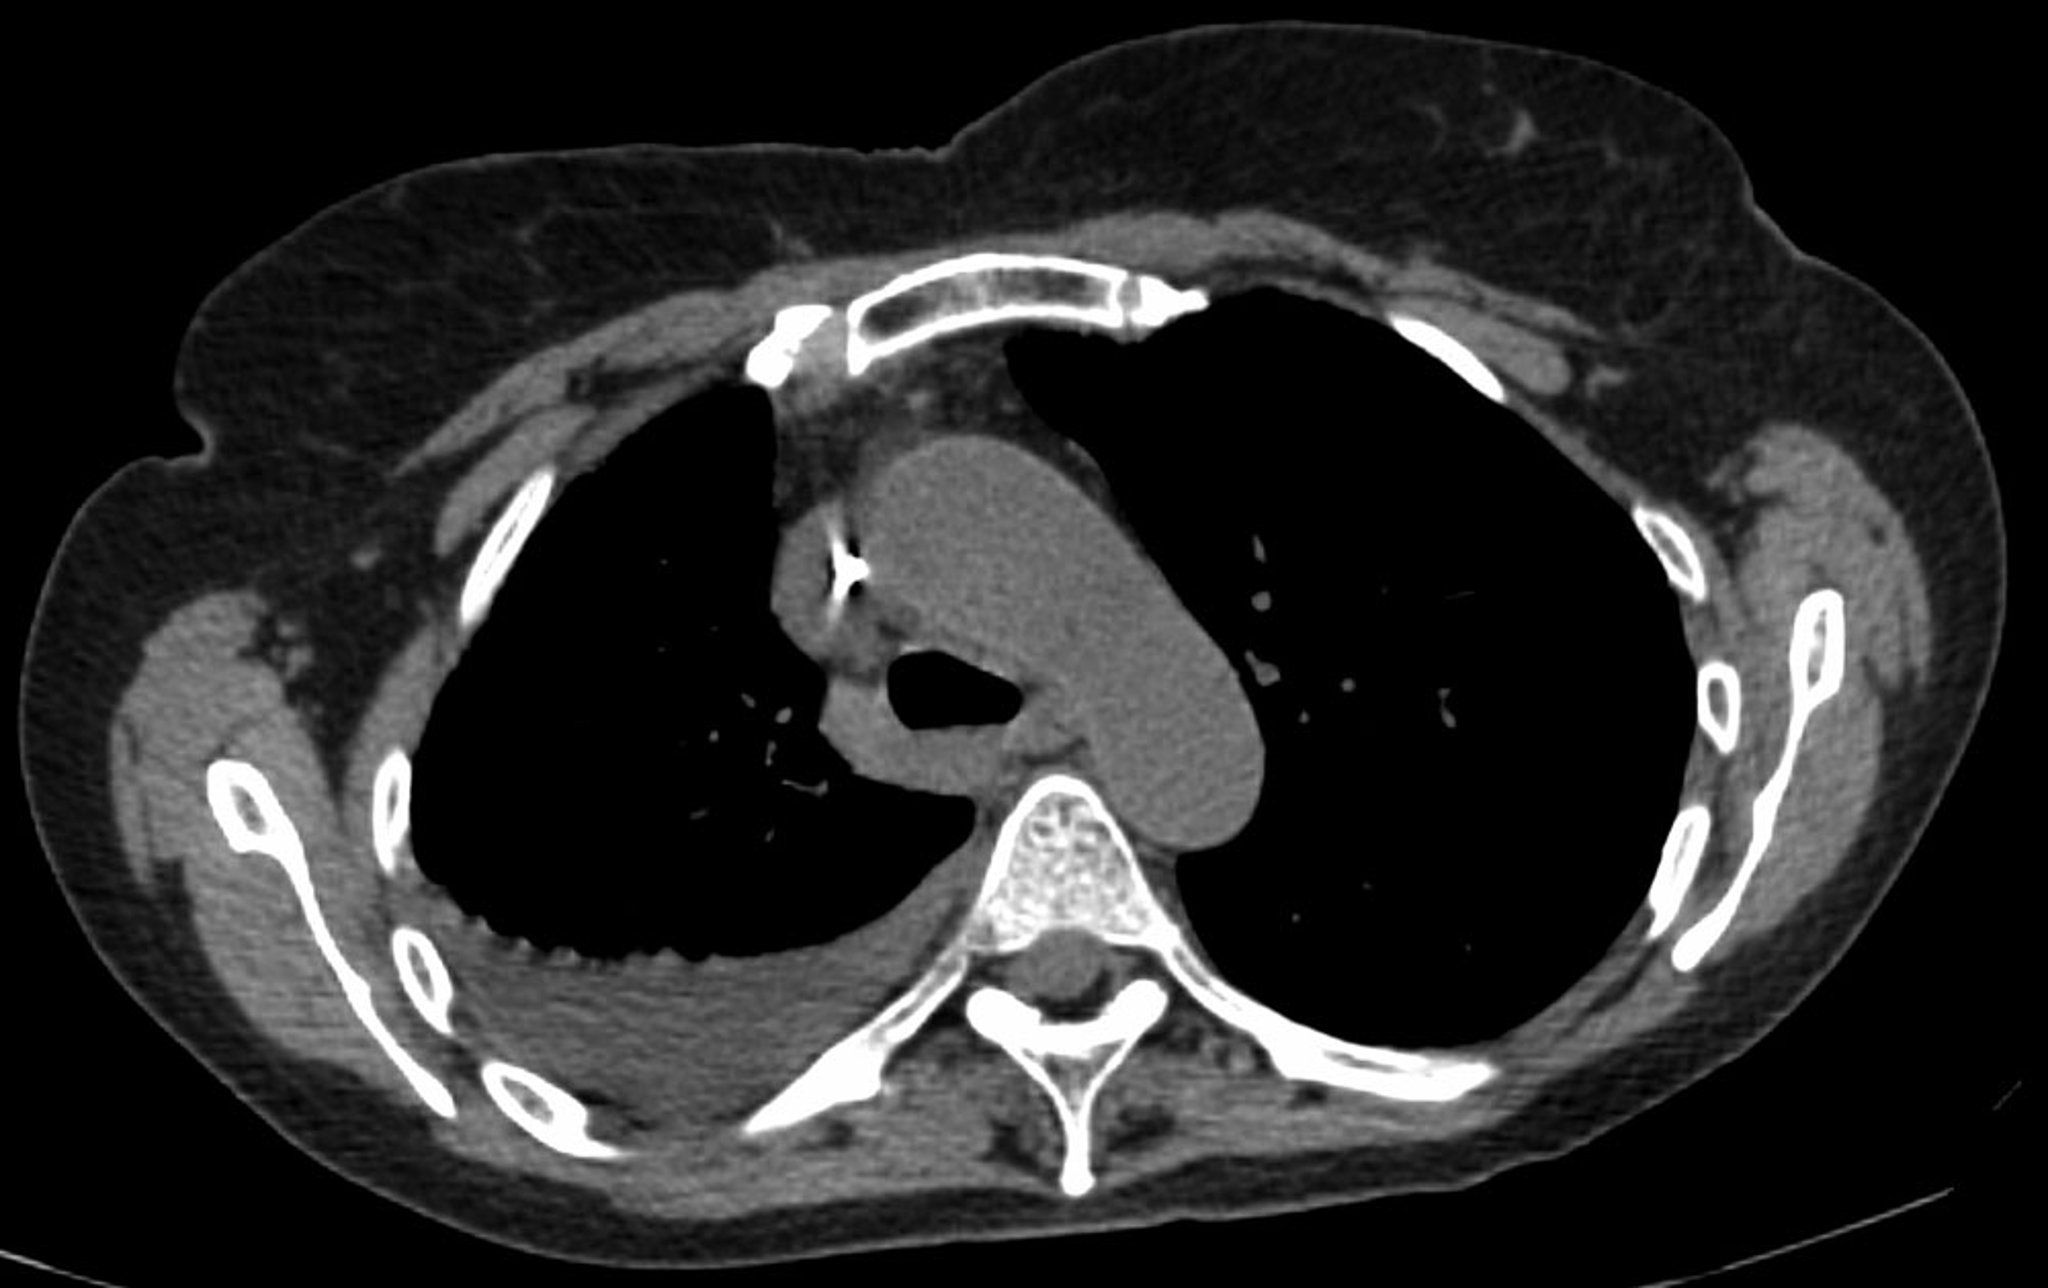

静脉造影 CT 是一项有价值的下一步检查,它可以提供胸膜增强和潜在胸膜结节的信息。(非增强CT可用于初步评估,但不能排除恶性肿瘤或感染。)当肺部被积液遮挡时,或者当胸部x光片上的细节不足以区分腔积液和实体肿块时,带有静脉造影的CT对于评估下方肺实质的浸润或肿块是有价值的。

影像学检查 也可能对诊断有所帮助。如果胸水分析后诊断仍不清楚,则需要进行静脉造影增强 CT 来评估胸膜强化、胸膜结节、肺部浸润或纵隔病变。CT肺血管造影可用于评估可疑的肺栓塞。肺栓塞的发现表明需要长期抗凝治疗。胸膜结节和增厚表明需要胸膜活检(胸腔镜或图像引导)。根据可疑原因,肺部浸润或病变的存在可能表明需要进行支气管镜检查或图像引导的肺活检。

• 如果胸部X线密度不能确定是积液或肺实质浸润或积液是否是包裹性的,则应该做侧卧位X线,胸部CT或超声检查。